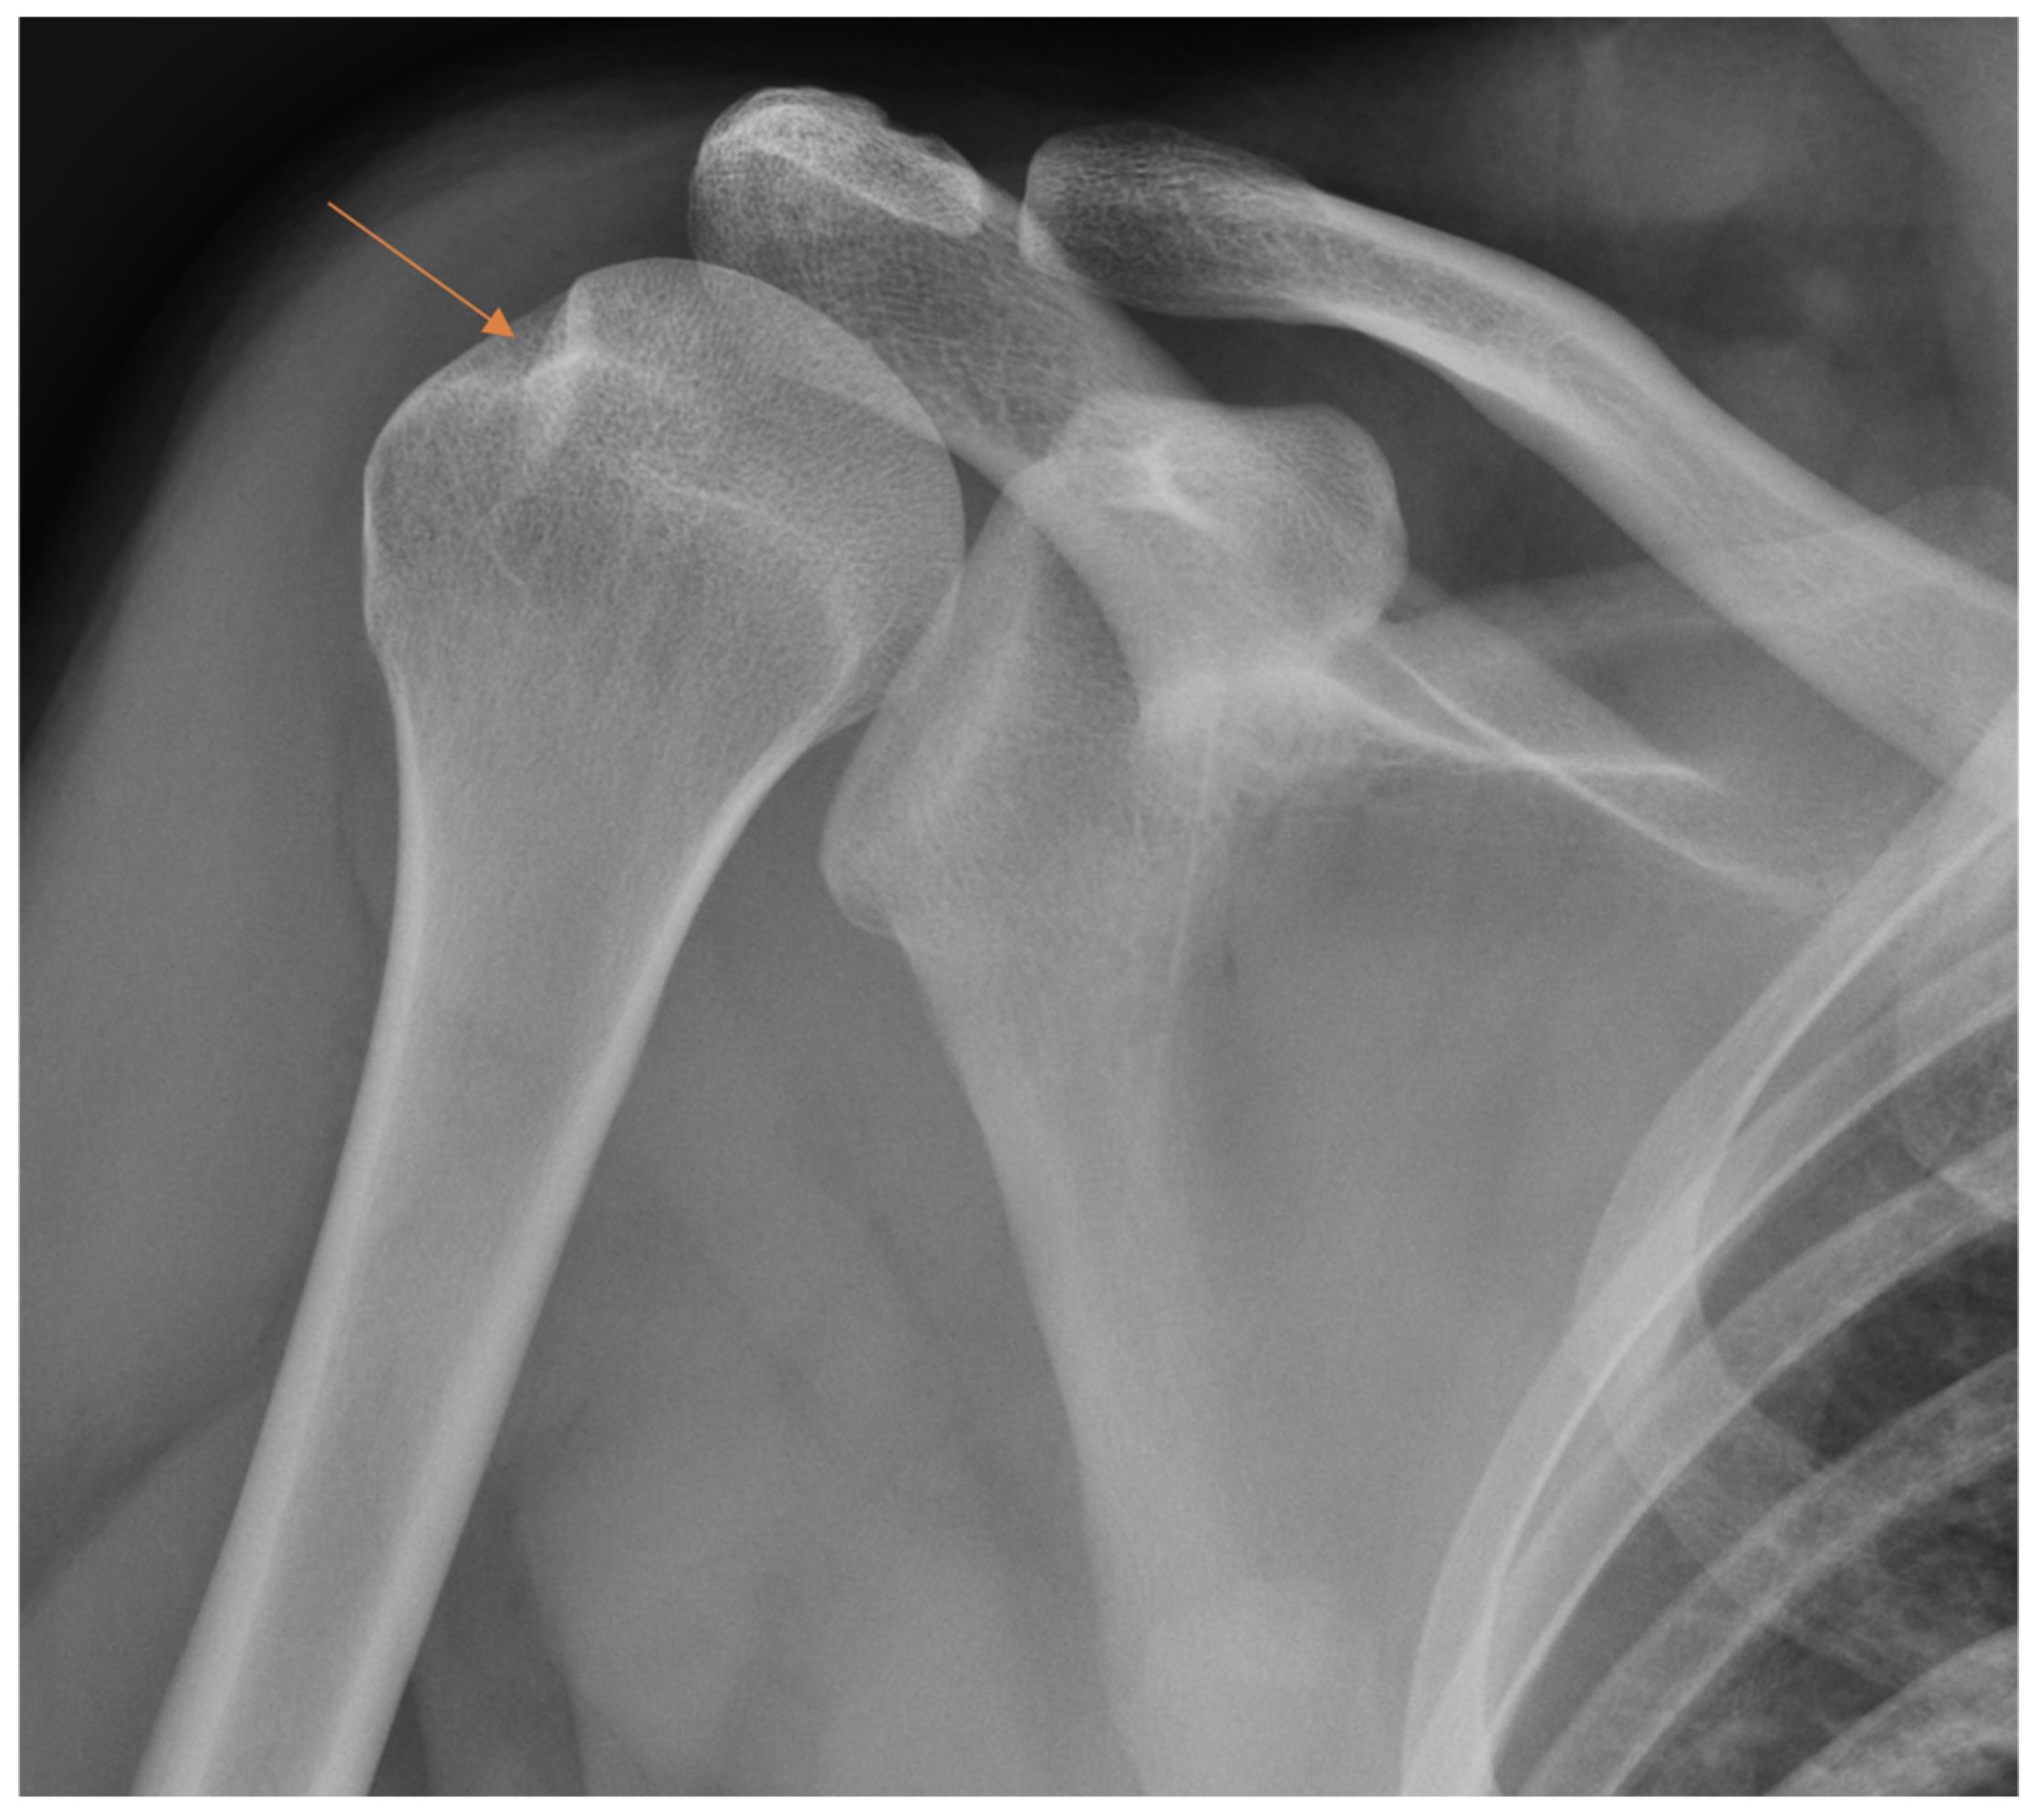

From all the missed findings in the radiographs, 70% (n = 44) were interpreted as having an impact on patient care (p = 0.02), but this did not differ between the radiology specialists and the residents. Findings missed by the radiology specialists (Figure 4 and Figure 5) affected patient care in 71% of cases and overcalls in 31% of cases. Findings missed by the residents (Figure 6) affected patient care in 69% of cases and overcalls in 47% of cases. From all the overcalls in the radiographs, 40% (n = 12) seemed to have an impact on patient care. The most common impact on patient care was a lack of the necessary control study (40%), followed by an unnecessary control study (14%). Interpretation error rarely led to unnecessary operative treatment (1%).

Figure 5.

Patient with anterior shoulder dislocation. The radiology specialist missed a Hill–Sachs lesion (arrow) that resulted in delay in patient treatment.